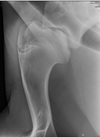

Figure 98-6. Mediolateral radiograph of the shoulder joint. A displaced fracture of the supraglenoid tubercle is seen. The fracture fragment is displaced craniad and dorsad.

Figure 98-8. Mediolateral radiograph of the same shoulder joint depicted in Figure 98-6 after internal fixation of the fracture using two 4-hole, 4.5-mm narrow locking compression plates with 5.0-mm locking head screws.